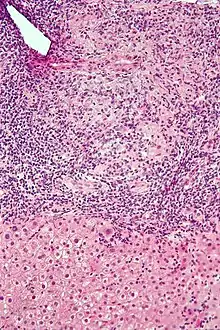

Histology of primary biliary cholangitis × 200 liver biopsy

Intermediate magnification micrograph of PBC showing bile duct inflammation and periductal granulomas. Liver biopsy. H&E stain.

On microscopic examination of liver biopsy specimens, PBC is characterized by chronic, non-suppurative inflammation, which surrounds and destroys interlobular and septal bile ducts. These histopathologic findings in primary biliary cholangitis include the following:[34]

- Inflammation of the bile ducts, characterized by intraepithelial lymphocytes, and

- Periductal epithelioid granulomata.

- Proliferation of bile ductules

- Fibrosis (scarring)

The Ludwig and Scheuer scoring systems have historically been used to stratify four (1–4) ‘stages’ of PBC, with stage 4 indicating the presence of cirrhosis. In the new system of Nakanuma, the stage of disease is based on fibrosis, bile duct loss and features of cholate-stasis, i.e. deposition of orcein-positive granules, whereas the grade of necroinflammatory activity is based on cholangitis and interface hepatitis. The accumulation of orcein-positive granules occurs evenly across the PBC liver, which means that staging using the Nakanuma system is more reliable regarding sampling variability.